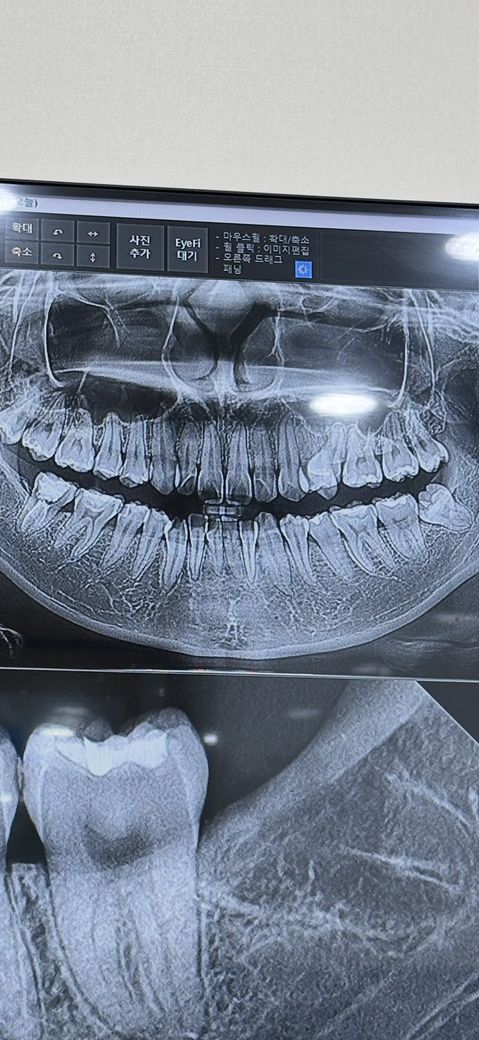

이빨이 깨져서 치과에 갔는데 저 엑스레이 사진에서 충치가 심하게 보이나요?

이빨이 깨져서 치과에 방문했는데 깨진 부위가 충치 때문에 썩어서 깨졌다고 하더라고요 깨진부위를 때울려면도자기?를 해서 빨간색 선 만큼 깍고 만약 깍고 나서 신경이 보인다면 신경치료를 해야 한다고 하시는데 저 엑스레이 사진에서 충치가 좀 심한가요? ㅜㅜ

그리고 예전 3년 전쯤 오른쪽 맨 끝 어금니

신경치료를 했는데 돈이 없어서 크라운을 안씌웠는데 현재는 어쩔 도리가 없고 나중에 치아가 깨졌을때 임플란트 해야 한다고 하시는데 지금이라도 크라운을 씌우면 살릴수 있을까요? ㅠㅠ

충치가 많이 진행된거 같고 일단은 신경치료를 하지 않고 치료를 해보겟지만 신경치료 가능성이 있어 보입니다.

충치도 있고 치아도 옆면이 깨져나가서 인레이를 하자고 한것이고 여기서 치료하다가 신경이 노출되면 신경치료를 해야합니다